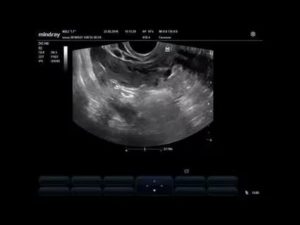

Во время гинекологического осмотра врач может найти уплотнения, образовавшиеся в области придатков. Определить наличие кист во время беременности можно на УЗИ с использованием вагинального датчика.

- УЗИ брюшной полости показывает объемные эхогенные новообразования и дает оценку их размерам. Во время беременности на УЗИ достаточно сложно определить желтое тело, из-за его небольшой величины;

Каждый раз при осуществлении УЗИ организма беременной женщины доктор дополнительно оценивает видимость и размеры железы, потому что это очень важно для полноценного вынашивания и правильного обеспечения жизни ребенка.